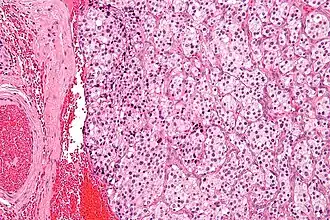

![]() Micrografía de un tumor de cuerpo carotídeo (un tipo de paraganglioma). | ||